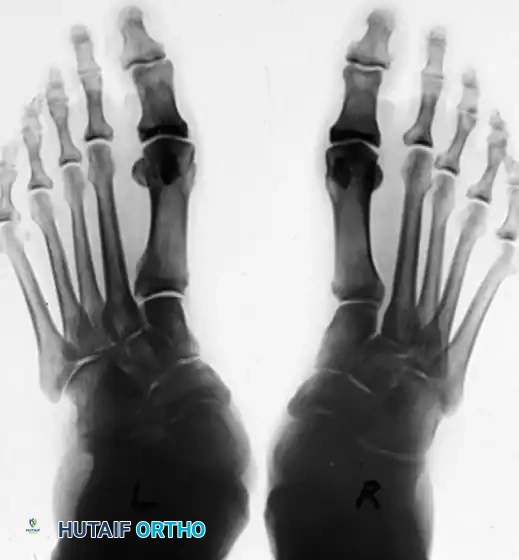

Patient with bilateral pes planus demonstrating the classic loss of the medial longitudinal arch.

Weight-bearing posterior view showing the three components of deformity: hindfoot valgus, forefoot abduction, and arch collapse. The Achilles tendon tightens in long-standing deformity, exacerbating heel valgus.

1. The "Too Many Toes" Sign: Viewed from behind, forefoot abduction allows the examiner to see more toes on the lateral side of the affected foot compared to the normal side.